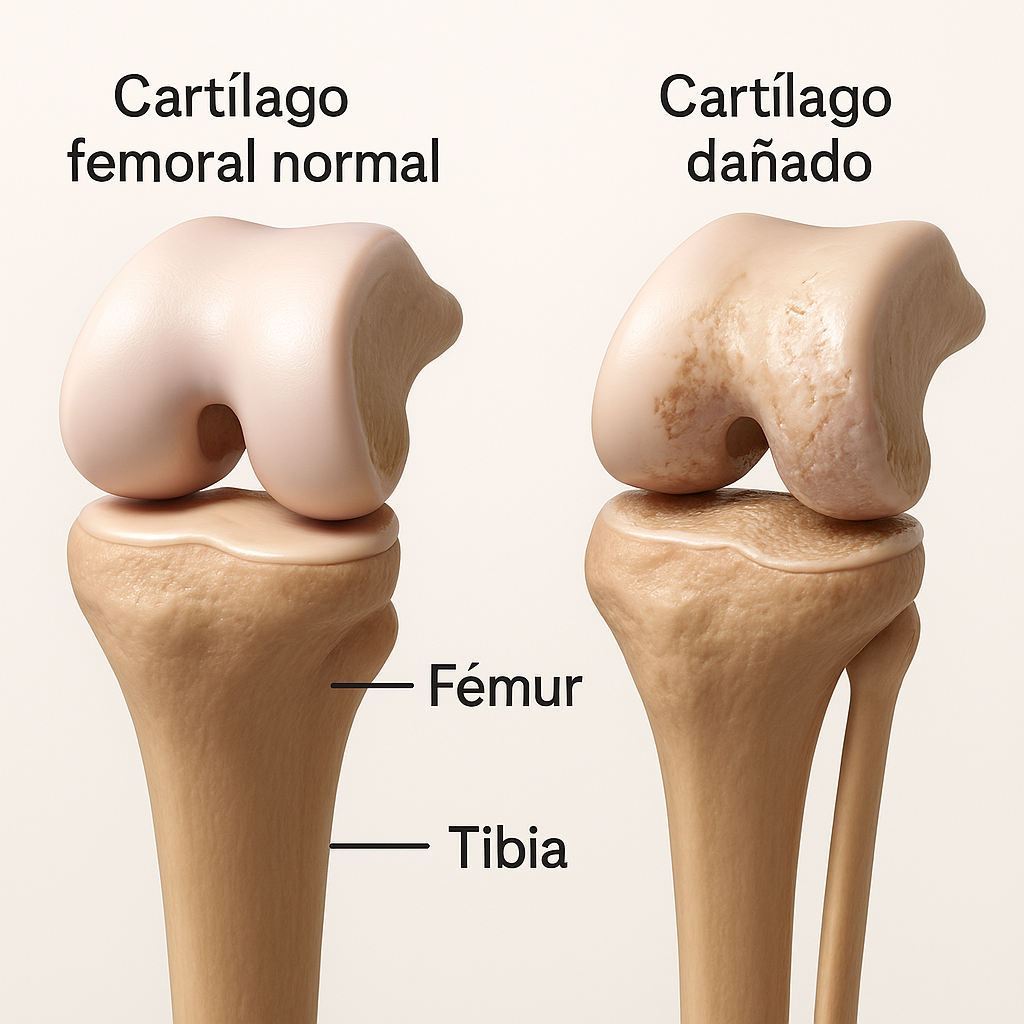

Lesiones del Cartílago Articular por gonartrosis

¿Qué es la Gonartrosis?

Es una enfermedad degenerativa crónica de la rodilla, donde el cartílago articular se desgasta progresivamente. Este deterioro causa que los huesos rocen, generando dolor, inflamación y limitación del movimiento, y su prevalencia aumenta con la edad.

Lesiones deportivas del Cartílago Articular

¿Qué son?

Son daños al tejido liso y elástico que recubre los extremos de los huesos en las articulaciones, causado por traumatismos, sobrecarga o desgaste. Afectan la capacidad de movimiento y amortiguación de la articulación, y el cartílago tiene poca capacidad de regeneración.